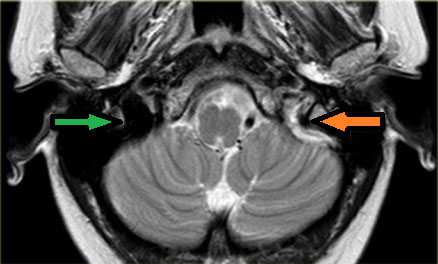

МРТ головного мозга: справа (зеленая стрелка) на Т2-взвешенном изображении отмечается имеющийся в норме феномен «пустоты потока» от правого сигмовидного синуса и яремной Вены. Слева (оранжевая стрелка) отмечается аномально высокий сигнал, в результате, вероятнее, тромбоза. Для подтверждения синус-тромбоза и окончательного определения локализации и протяженности тромбоза необходимо проведение МР-венографии.

МРТ головного мозга: отмечается сочетание вазогенного (оранжевая стрелка), цитотоксического отека и кровоизлияния (зеленая стрелка). Данная МР-картина, а также расположение патологической зоны в проекции височной доли, заставляет задуматься о геморрагическом венозном НМК вследствие тромбоза вены Лаббе. Для подтверждения необходимо проведение МР-венографии или МРТ с контрастным усилением.